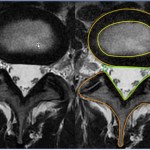

Spine Concepts: Disc Herniation

Courtesy: Prof Nabil Ebraheim, University of Toledo, Ohio, USA